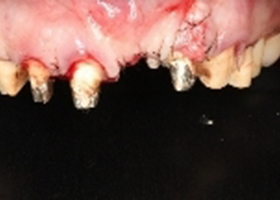

病患就診前口內照片。

右側假牙過短、左側正中門牙缺牙、左側側門牙牙齦萎縮,且牙冠過長。